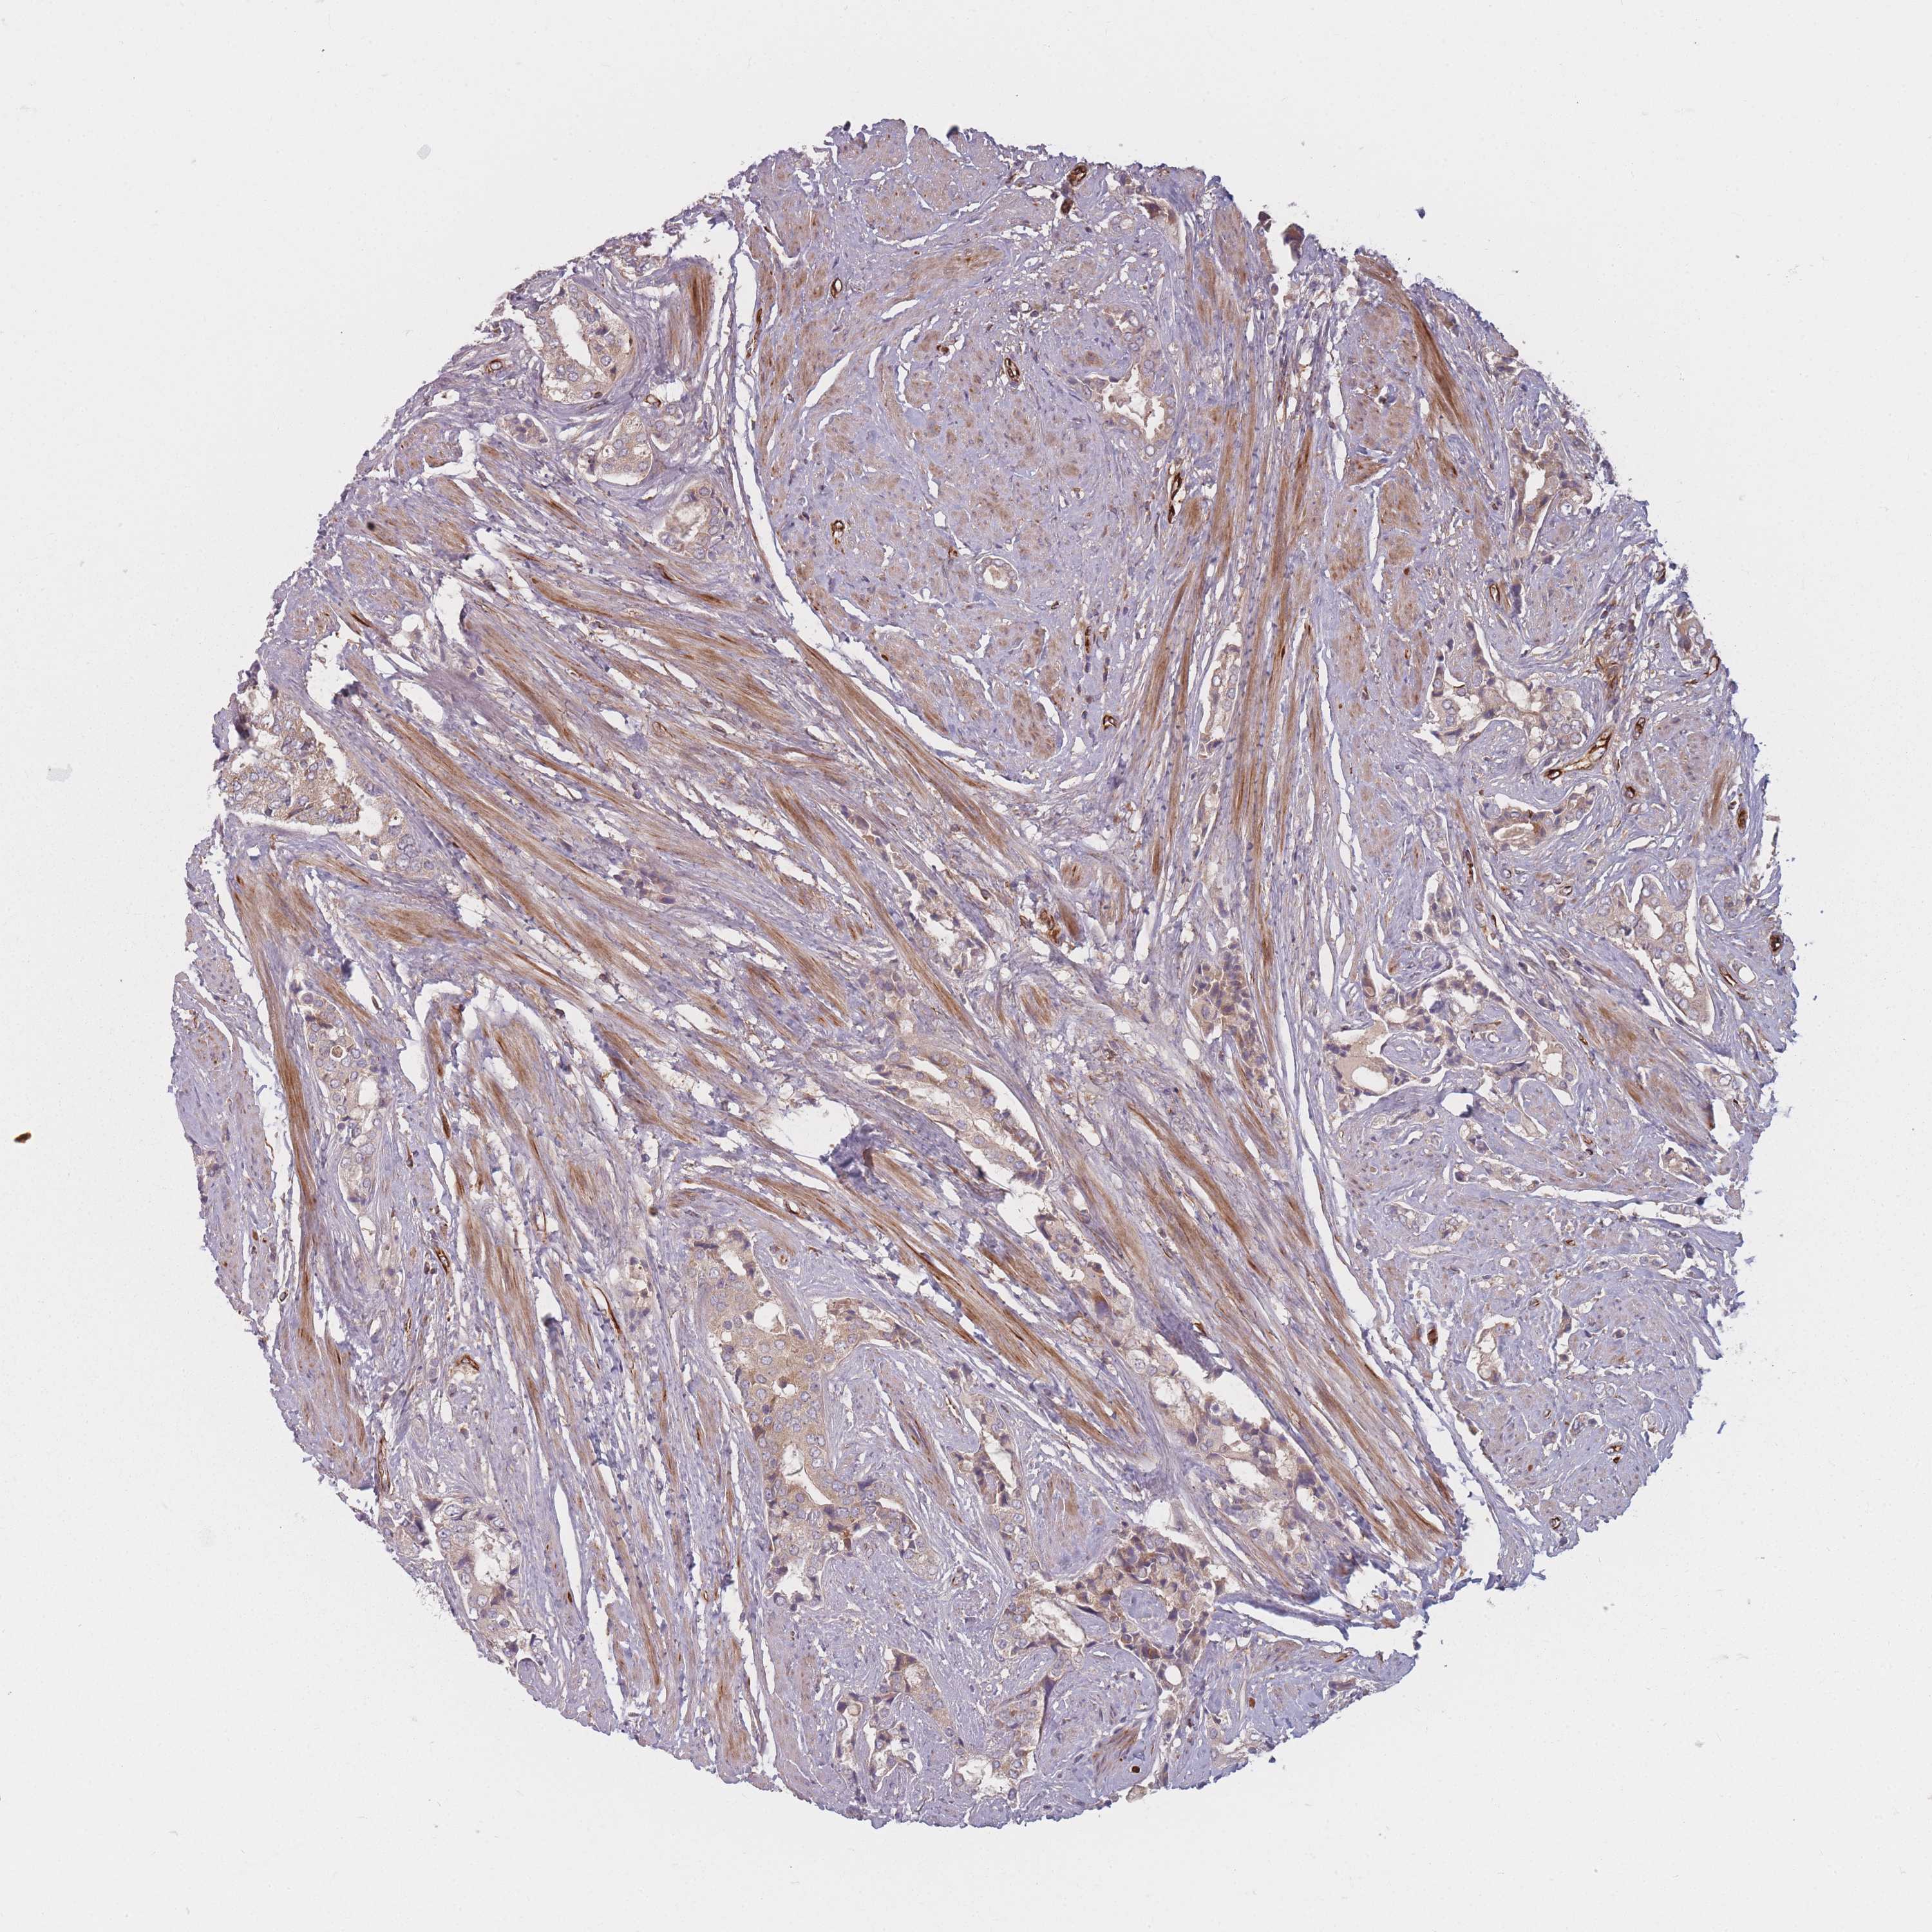

PROSTATE CANCER - Protein expressioni

A mouse-over function shows sample information and annotation data. Click on an image to view it in a full screen mode. Samples can be filtered based on level of antibody staining by selecting one or several of the following categories: high, medium, low and not detected. The assay and annotation is described here.

Note that samples used for immunohistochemistry by the Human Protein Atlas do not correspond to samples in the TCGA dataset.

Antibody stainingi

Antibody staining in the annotated cell types in the current human tissue is reported as not detected, low, medium, or high, based on conventional immunohistochemistry profiling in selected tissues. This score is based on the combination of the staining intensity and fraction of stained cells.

Each image is clickable and will lead to virtual microscopy that enables deeper exploration of all samples and also displays staining intensity scores, fraction scores and subcellular localization as well as patient and tissue information for each sample.

Antibody HPA050138

Staining

High

Medium

Low

Not detected

Intensity

Strong

Moderate

Weak

Negative

Quantity

>75%

75%-25%

<25%

None

Location

Nuclear

Cytoplasmic/membranous

Cytoplasmic/membranous,nuclear

Adenocarcinoma, High grade

Adenocarcinoma, Low grade